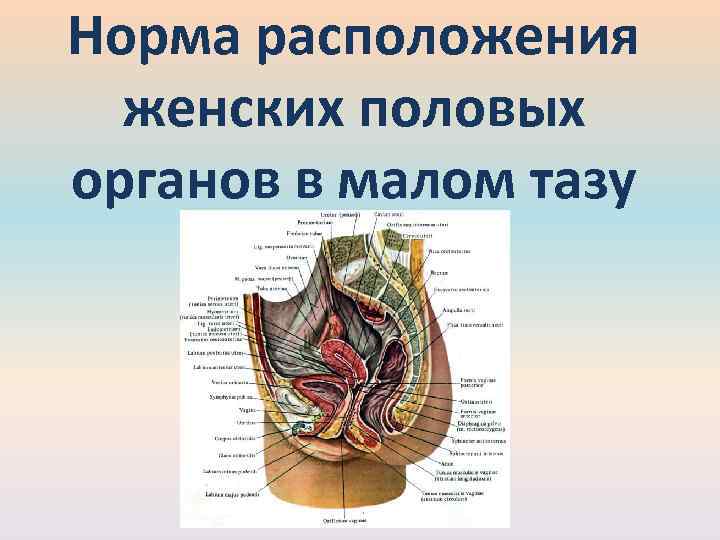

Анатомия малого таза: детальные схемы и изображения